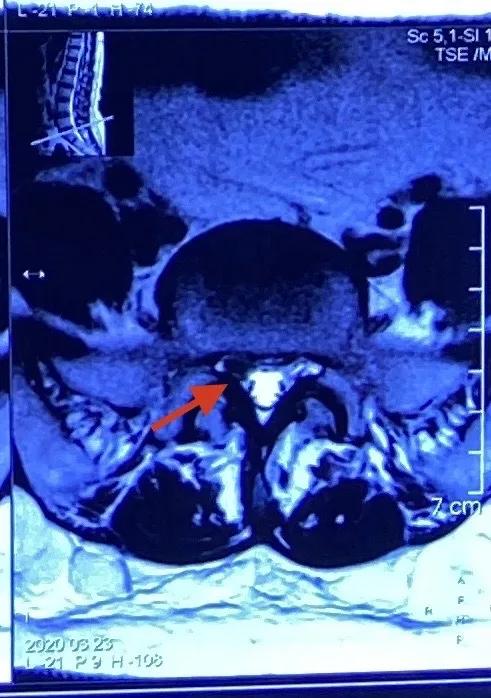

术前MRI提示:L5/S1椎间盘突出

神经根明显受压